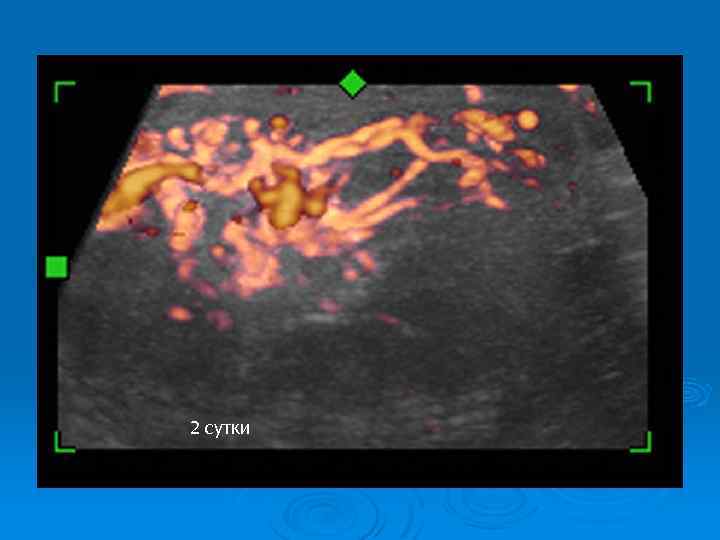

До операции: перекрут 1100 градусов, 14 часов

2 сутки

Перекрут яичка: наблюдение в динамике Ø Регулярный УЗИ контроль Ø Оценка гормонального статуса Ø Исследование эякулята